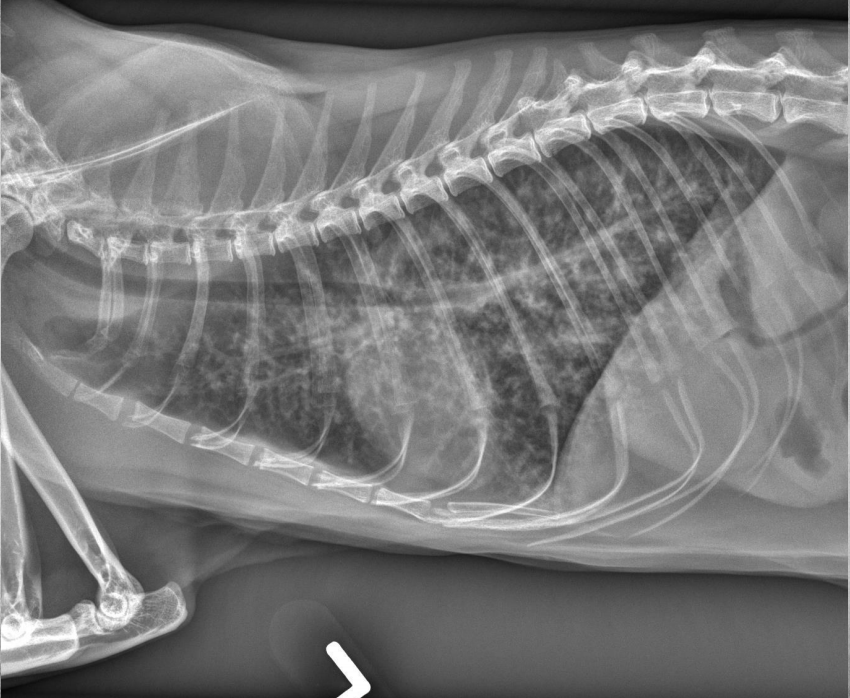

● 3 mo Bernese Mountain Dog

● Acute onset of respiratory distress and hemoptysis

● Vomited blue/purple material 10 days prior, was normal within the meantime

alveolar pattern (black trees in snow storm but blood vessels not visible)

aerophagia

bleeding into lung parenchyma secondary to rat poison ingestion